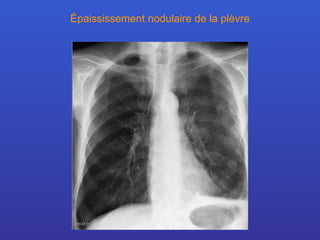

Épaississement nodulaire de la plèvre

Mésothéliome